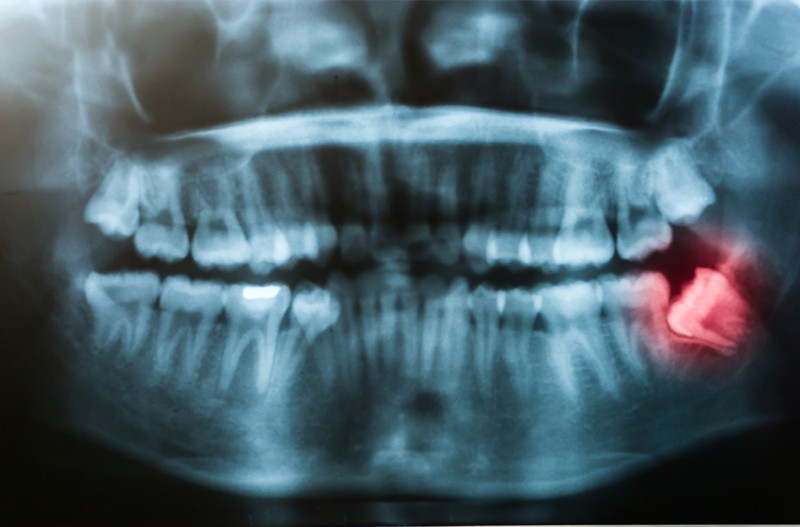

1. Khi răng khôn nằm ẩn hoàn toàn trong nướu: Có thể gây một loạt các triệu chứng khó chịu và nguy cơ nhiễm trùng,

vì vi khuẩn không thể thoát ra ngoài và tạo điều kiện cho việc phát triển các bệnh lý.

2. Khi chỉ nhú một phần ra khỏi nướu: Việc vệ sinh răng miệng trở nên khó khăn và tạo điều kiện cho vi khuẩn sinh sôi, làm gia tăng nguy cơ viêm nhiễm.

3. Khi chúng mọc chen chúc: Có thể gây hư hại cho các răng lân cận và dẫn đến các vấn đề về chức năng ăn nhai và thẩm mỹ.

4. Nếu bạn cảm thấy đau đớn hoặc nhiễm trùng tái phát: Đây chính là dấu hiệu rõ ràng cho việc cần tham khảo ý kiến bác sĩ để đưa ra quyết định đúng đắn cho sức khỏe răng miệng của bạn.